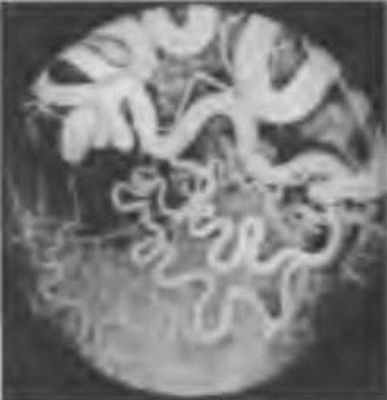

В раннем возрасте рацемозная гемангиома характеризуется монокулярным амаврозом, косоглазием. После 30 лет выявляется случайно. На глазном дне обычно в области диска зрительного нерва хорошо видны резко расширенные, извитые и полнокровные артерии и вены, соединяющиеся между собой. Мелкие сосуды (артериолы, капилляры и венулы) отсутствуют, что хорошо иллюстрирует ангиограмма (рис. 7.4).

Рис. 7.4. Ангиограмма. Рацемозная гемангиома сетчатки. Флюоресцируют резко расширенные и извитые сосуды

Пульсации сосудов нет. В сетчатке под сосудами — дистрофические изменения, участки гиперпигментации. Отслойка сетчатки отсутствует.